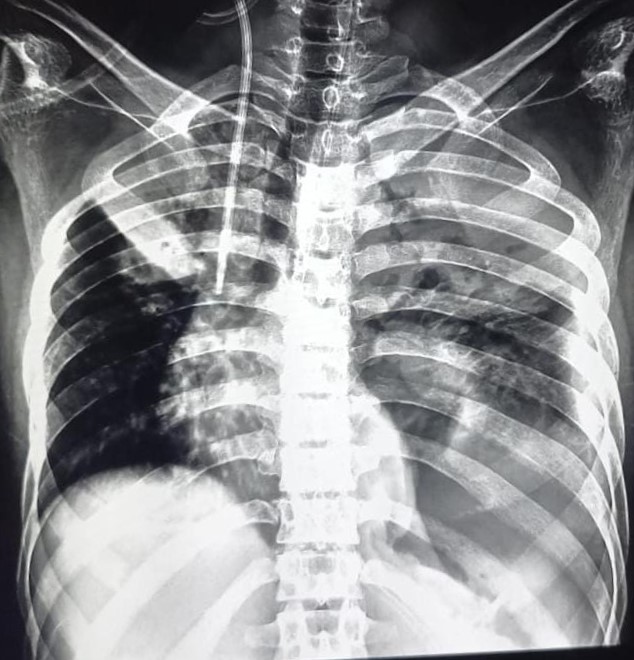

| 151 | IGGMC, Nagpur, Nagpur | P2 | 29-4321 | Chanda Bhowate | Consent taken on Paper | 42 Yrs. |

Provisional Diag : ?

Final Diag : (CxR- Right Sided Synpneumonic Effusion With Pulmonary Infiltration) |

Result awaited (Suspected TB/Non-TB) | Right CP Angle Blunting With Right Lower Zone In-Homogenous Opacity Present With Right Middle Zone/ Lower Zone Infiltration Present | Abnormality visible on x-ray |